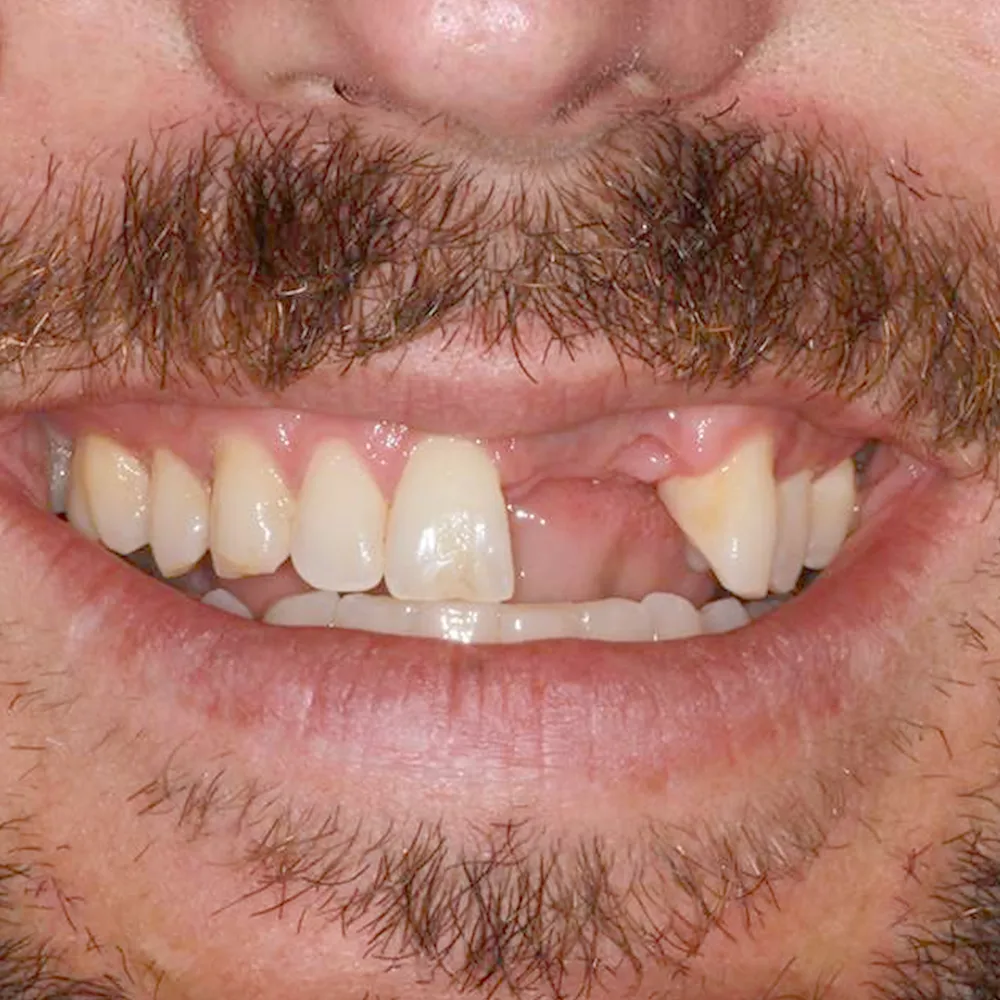

Real Stories, Real Results: Case Studies Showcasing How Our Personalized Approach Transforms Smiles and Lives

Complex Cases

Witness the Remarkable Changes We Can Achieve